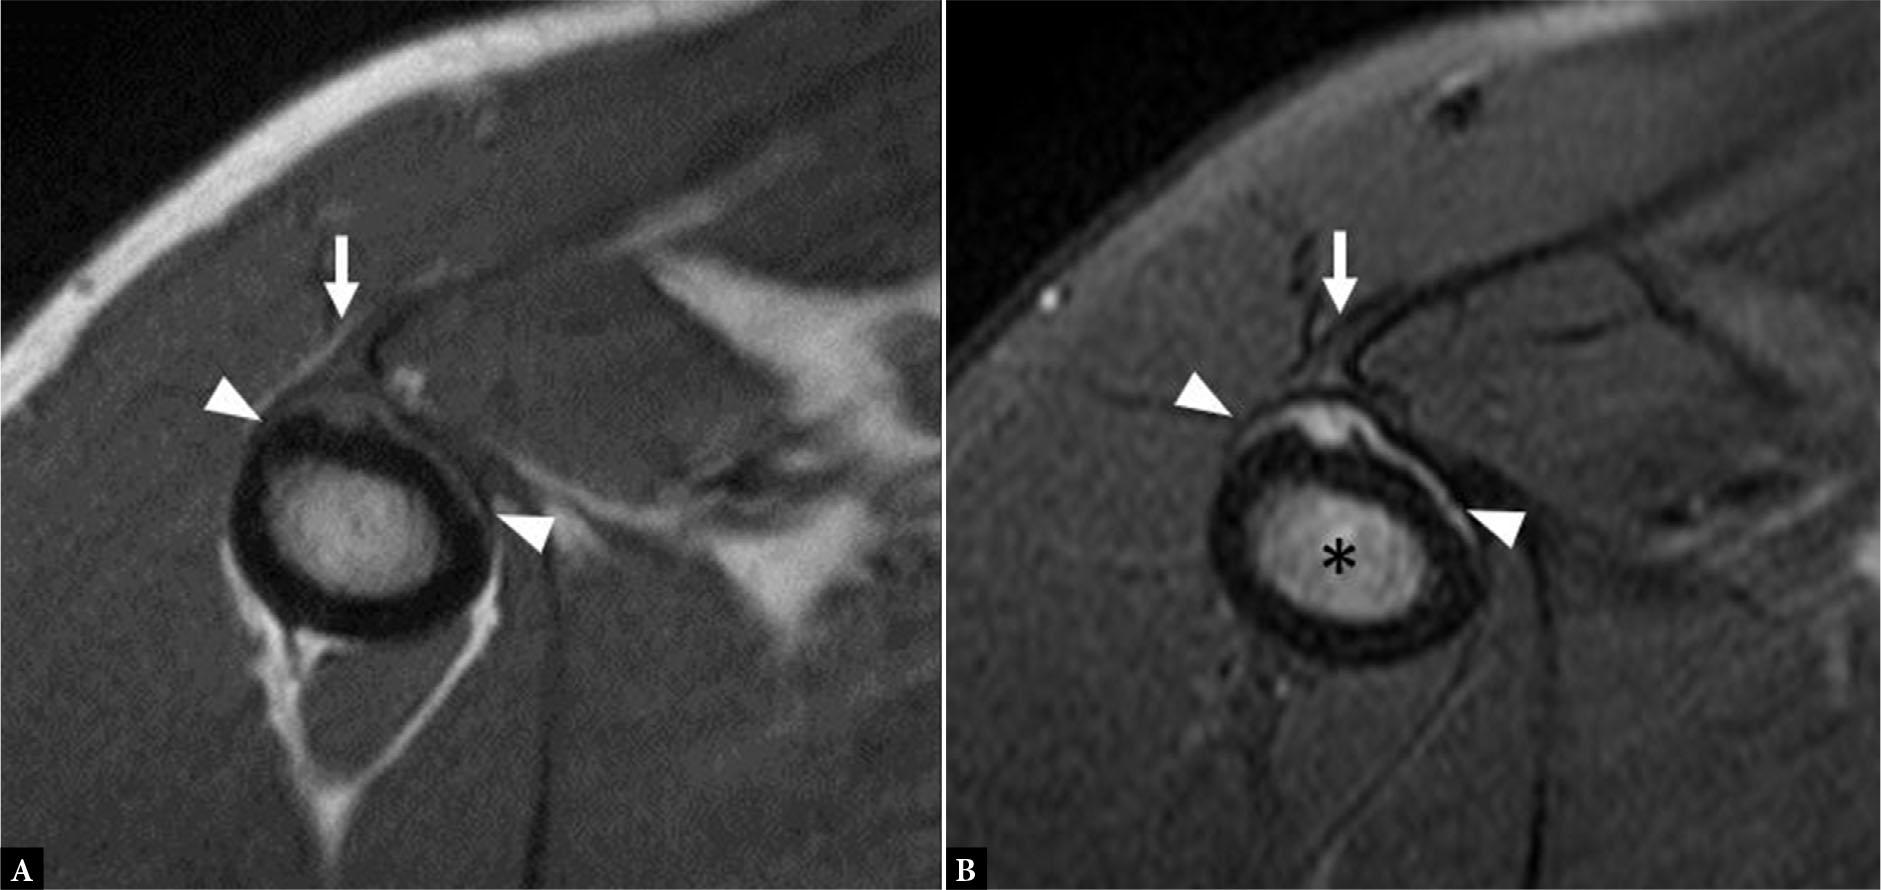

Fig. 11.

Axial T1 (A) and axial fluid-sensitive (B) MR images show periosteal thickening and edema (arrowheads) at the insertion of the PM tendon (arrow) with marrow edema (B – asterisk) consistent with mechanical tug-type changes without overt tendon tear